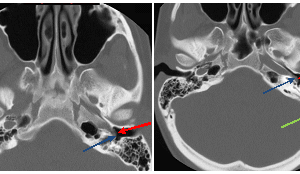

Aberrant Carotid Artery

Aberrant course of the internal carotid artery (a-ICA) is a congenital anomaly characterized by the displacement of the ICA posterior and lateral to its expected course. It results from the agenesis of... Read more »